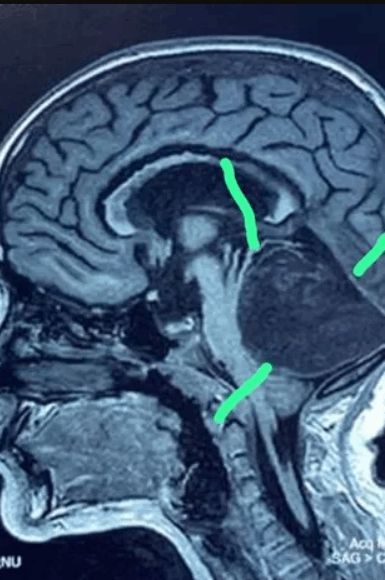

مقطع لدماغ الطفلة صورة لكتلة الشعر داخل دماغ الطفلة

وقالت وزارة الصحة القيرغيزية في بيان: "كان الورم يحتوي على خصلة من الشعر نمت على ما يبدو طوال حياة الطفلة قبل دخولها المستشفى، وكان للشعر جذر في الجزء السفلي من البطين وربما كان ناجما عن شذوذ في نمو ما قبل الولادة، وإن استمرار نمو الشعر من شأنه أن يشكل تهديدا لصحة المريضة".